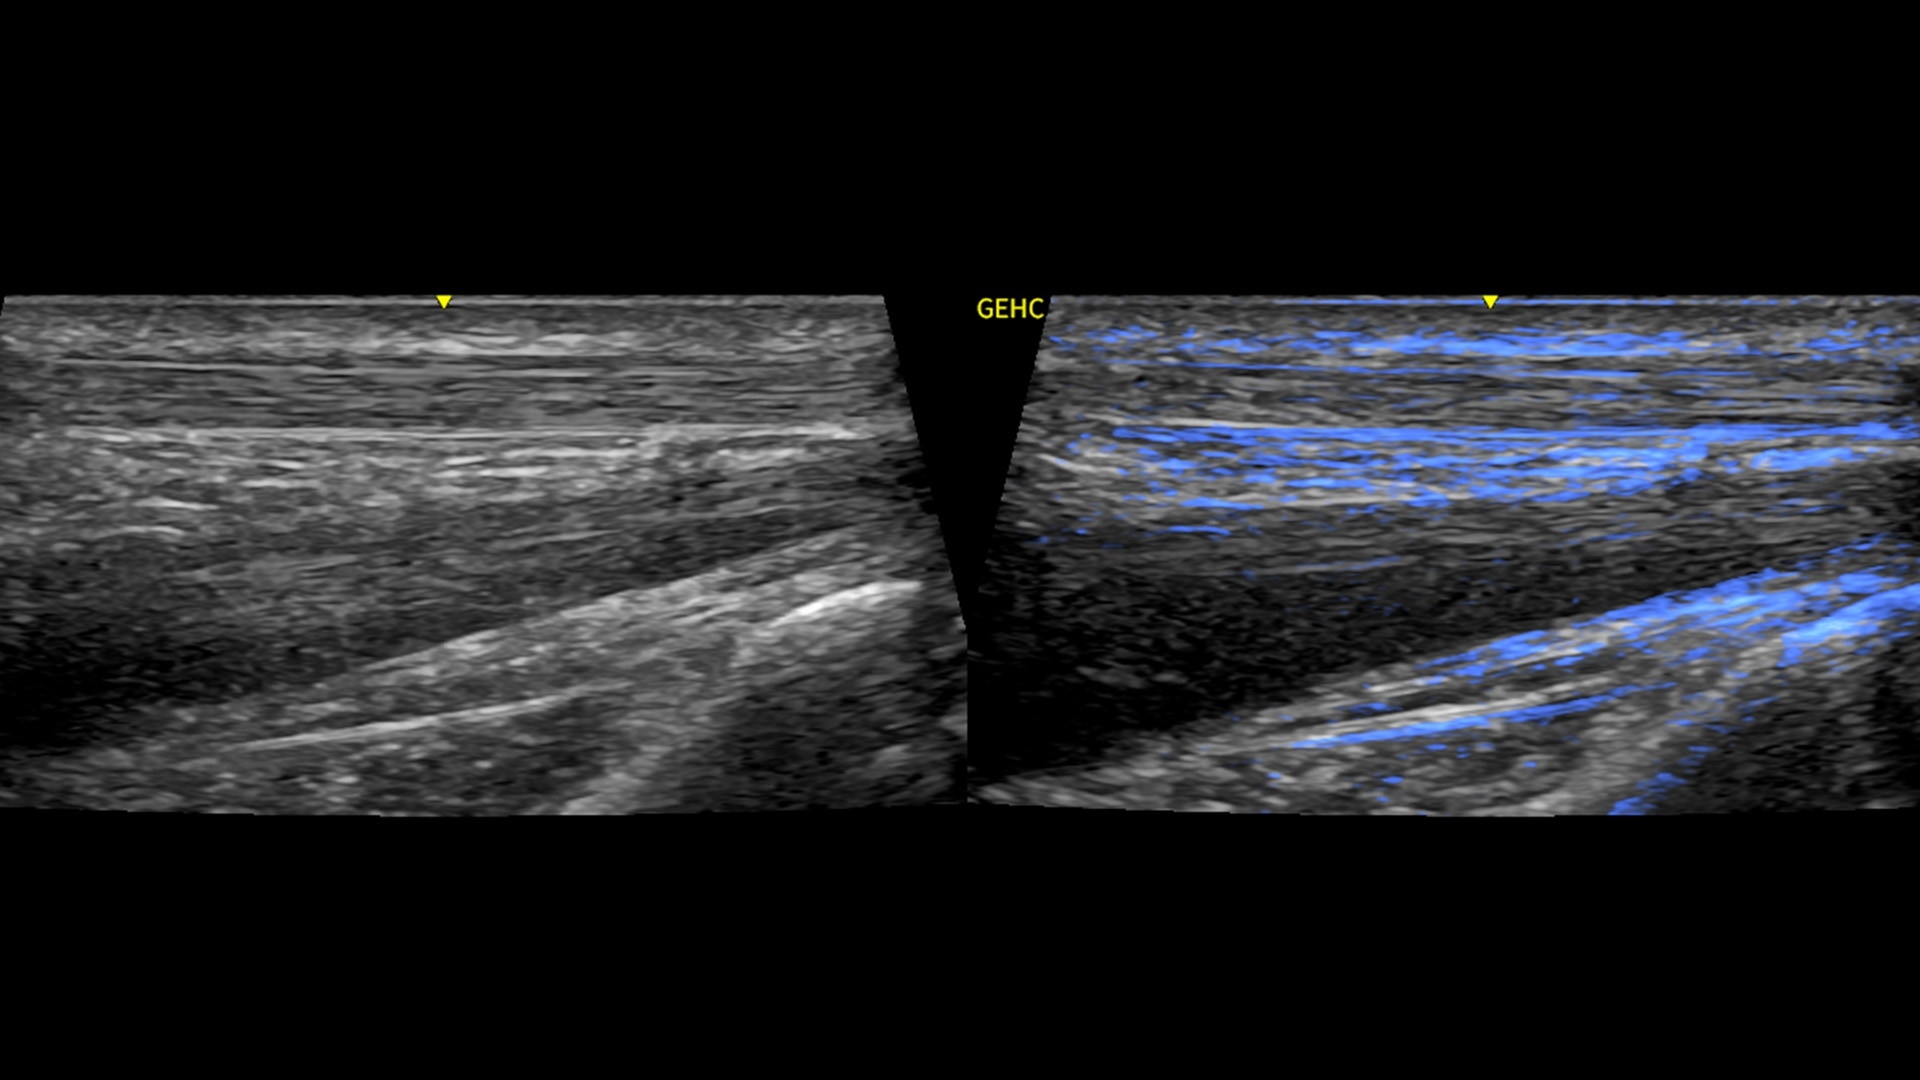

• Optimize images while scanning with Whizz clinical features, easily improve Color Doppler with Whizz Color Flow, and view scans in the image style that suits your preference with Whizz Easy Style